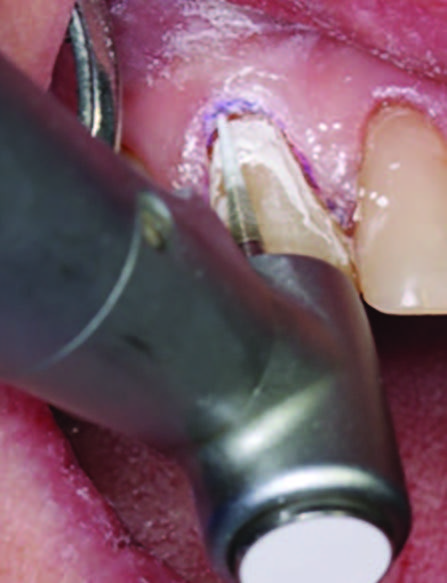

Figure 3. Application of caries indicator dye to identify the remaining infected tissue beneath the dislodged composite.

Figure 4. Preparation of the lesion is completed with diamond bur and starburst beveling pattern to enhance aesthetic blending.